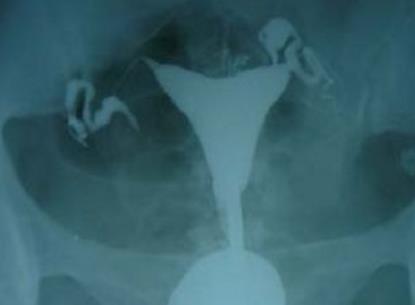

男女婚后不孕,经常一检查就得出是女性输卵管积水导致,医生解释,目前输卵管积水只是医生上的影象学诊断,是指注入子宫输卵管一定量的造影剂,在X光的显影下显示输卵